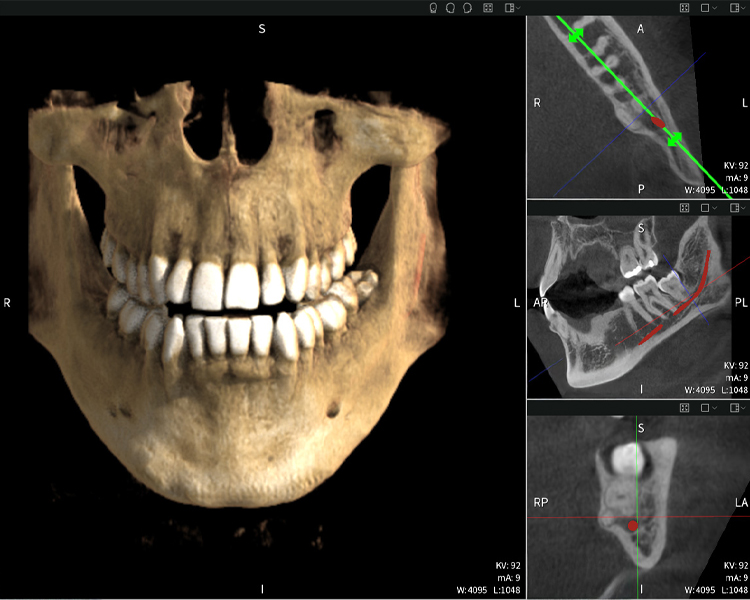

Figura c: Resultados de imagen de Seethrough Max, sobre un fondo negro.

Figura c:

Las figuras b–d muestran varias vistas de una reconstrucción 3D de la mandíbula, proporcionando una visión general completa de la anatomía mandibular, la posición de los nervios en relación con los dientes y permitiendo evaluar la simetría y alineación dentaria.

La figura d muestra el diente 48 previamente tratado, con la corona retirada y las raíces dejadas en proximidad al nervio, lo que ilustra el alto riesgo de daño nervioso.

Figura e: Resultados de imagen de Seethrough Max, sobre un fondo negro.

Figura e

Figura e: La radiografía panorámica sirve como herramienta de evaluación inicial, mostrando la posición general de los dientes, así como posibles cambios patológicos. Es notable que en el lado derecho (diente 48) se observa la situación posterior a una amputación de corona realizada por un profesional externo. Las dos raíces fuertemente curvadas permanecen en estrecha proximidad topográfica al nervio alveolar inferior dentro del hueso. Esto sugiere una decisión deliberada de evitar el mayor riesgo de lesión nerviosa durante una extracción completa y representa un hallazgo clínicamente relevante. En resumen, las tomografías CBCT con Seethrough Max proporcionan información crucial sobre la anatomía compleja y la relación crítica entre las muelas del juicio y el nervio alveolar inferior. Esta imagenología diagnóstica detallada preoperatoria es esencial para realizar procedimientos quirúrgicos seguros y exitosos en la región mandibular.